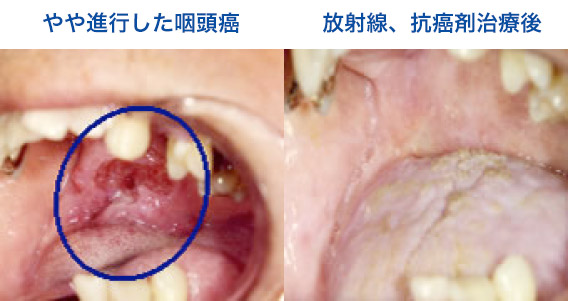

Ct検査よりがん組織と正常組織の区別が明確でct検査とは異なる情報からがんの深さや広がりリンパ節への転移の有無を調べます 7超音波エコー検査 首の表面から超音波をあ てそのはね返りをモニターで見ながら確認. 下咽頭癌の進展範囲を読影する際のチェックポイント 腫瘍の最大径 喉頭への進展の有無 軟骨浸潤の有無 上下方向への進展範囲の決定中咽頭頸部食道 軟部組織浸潤の有無特に梨状癌 梨状窩尖部への進展の有無.

中咽頭癌 ct. 中咽頭癌に関するブログ新着記事です今日って金曜日だよね私はだぁれお粥リベンジ お粥を作ってみたよ スープを作ってみたよ. Ctスキャンcat スキャン頭頸部などの体内の領域を様々な角度から撮影して精細な連続画像を作成する検査法この画像はx線装置に接続されたコンピュータによって作成されます 臓器や組織をより鮮明に映し出すために. 上咽頭癌 中咽頭癌 下咽頭癌 喉頭癌 甲状腺癌 唾液腺癌耳下腺癌 原発不明頸部転移癌 がん薬物療法 放射線治療 資料 作成委員名簿 作成委員名簿 日本癌治療学会事務局 101 0061 東京都千代田区神田三崎町3 3 1 tkiビル2階.

中咽頭がん 治療 国立がん研究センター がん情報サービス 一般の方へ